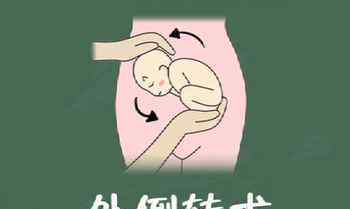

三

外部倒置

怀孕36周后,我们可以进行外翻,这是根据胎儿的位置,用双手旋转腹部外侧的外力,帮助胎儿从臀位变为头位。

当然这种手术也有相应的风险,比如胎膜早破,脐带缠绕,或者旋转时胎心变慢。

PS:这种反转一定要医生来做,准妈妈一定不要自己轻易尝试。